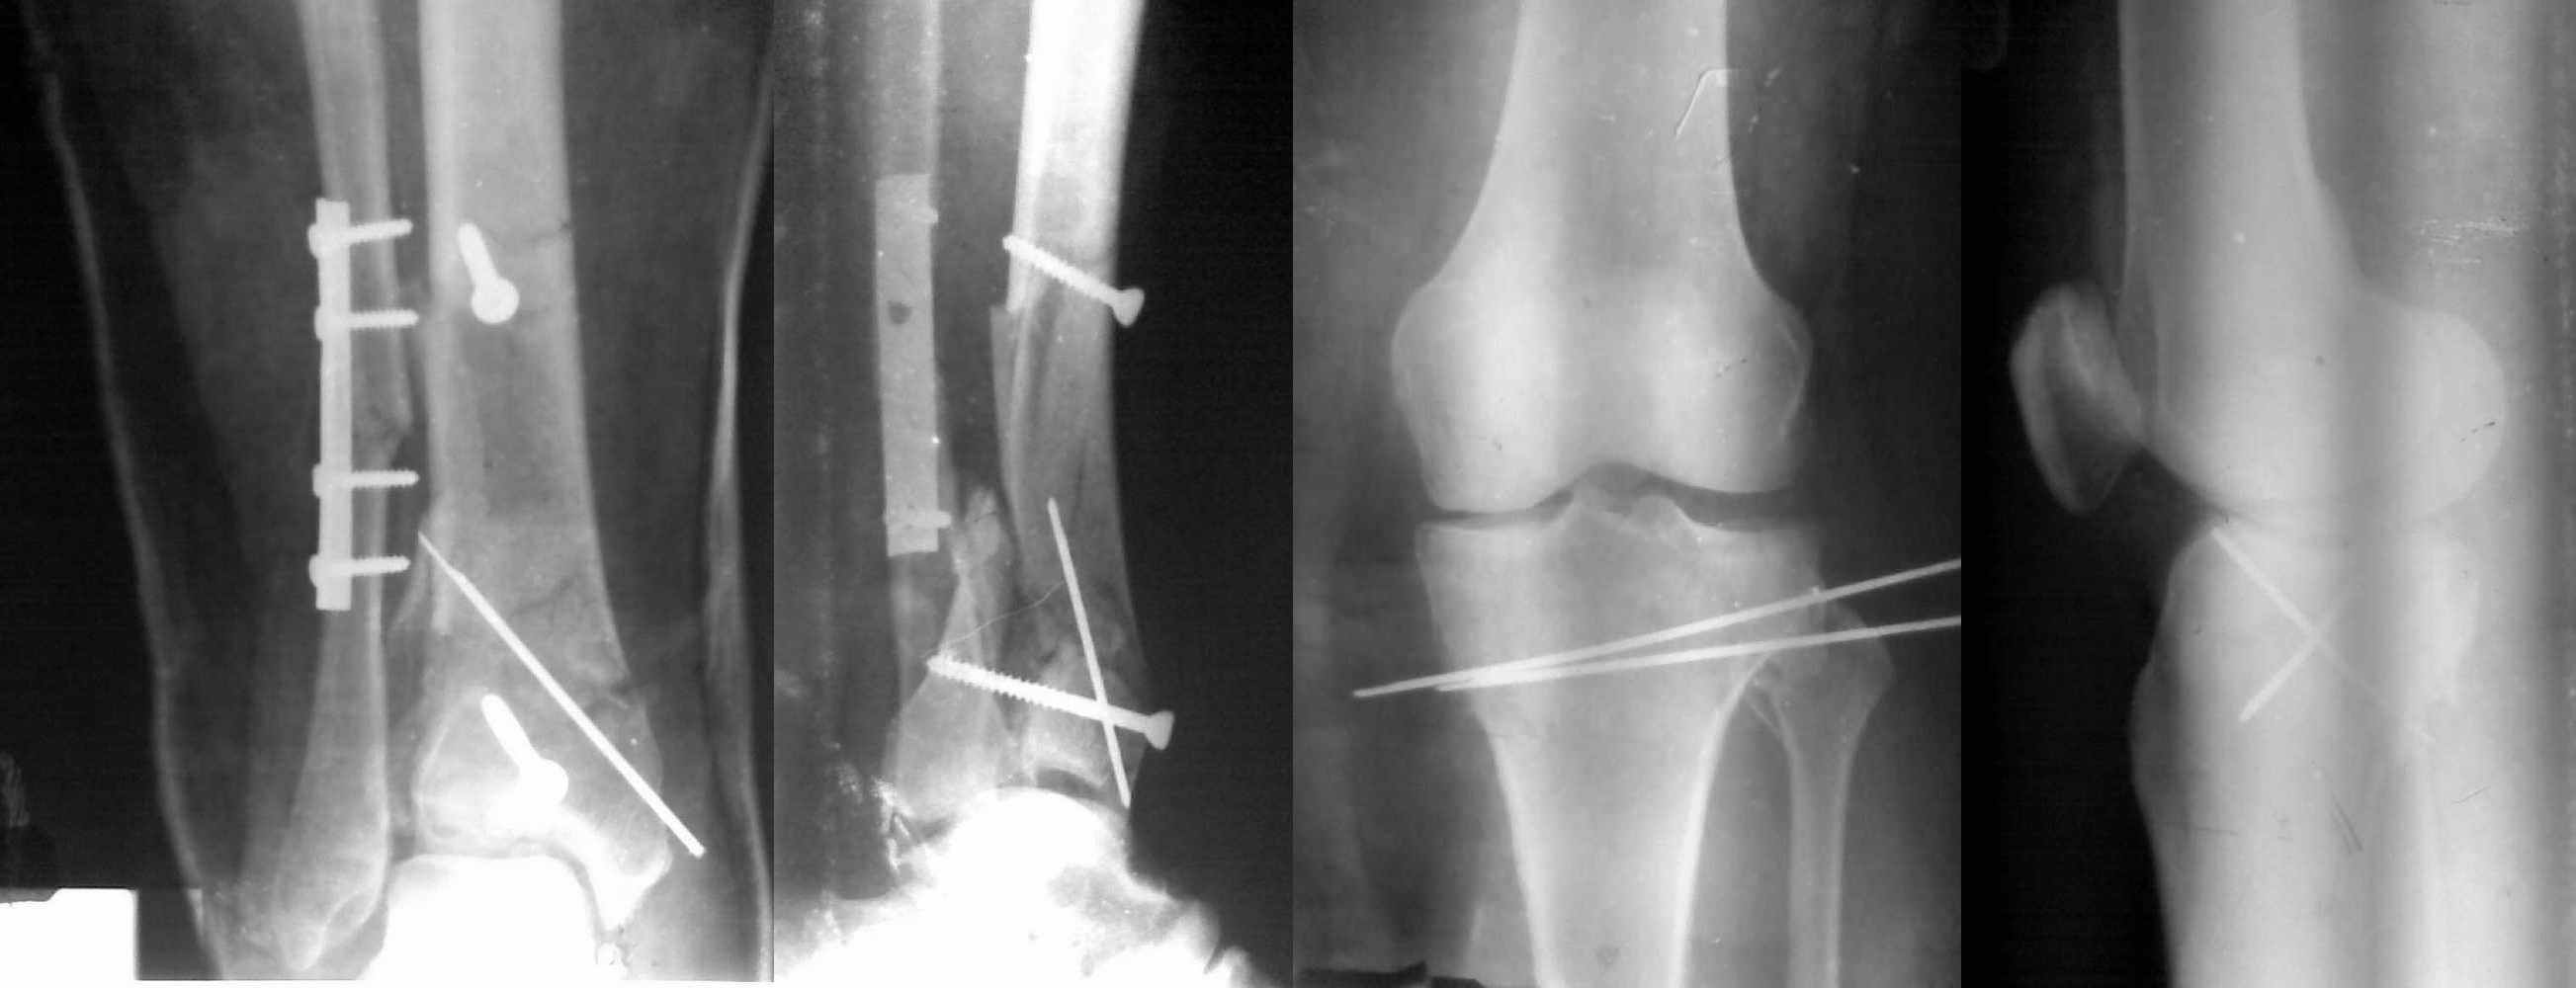

Пациентки прооперирована, результат чего на снимках. Выполнена открытая репозиция костей правой голени, синтез малоберцевой пластиной, б/берцевой винтами, имеющиеся фиксаторы не подходили, было принято решение репонировать отломки, синтез винтами, гипсовая повязка.

Мыщелок левой б/б кости репонирован закрыто, на контрольной рентгенограмме репозиция удовлетворительная, фиксировано спицами. гипсовая повязка.